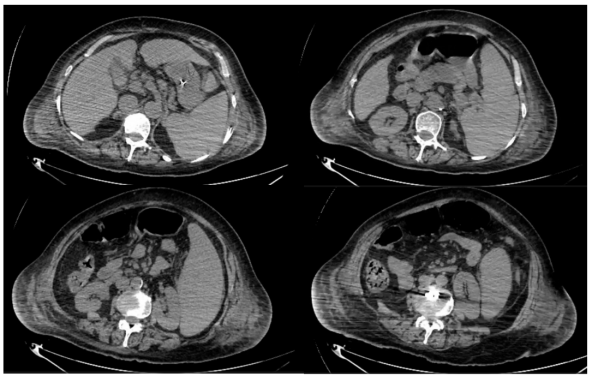

1)感染性休克:患者反复发热,炎症指标明显升高,胸部CT提示两肺感染,SOFA评分>2分,伴血压下降。感染诱发病情加重可能性较大,迅速调整治疗方案,予比阿培南抗感染治疗,2天复查炎症指标白细胞降至19.8×109/L,中性粒细胞19.16×109/LCRP 77.4 mg/L,PCT 13.8 ng/ml。复查胸部CT发现,患者肺部感染程度不能解释其感染性休克的表现3,考虑可能合并其他部位的感染。患者结合胆红素140 U/L(占总胆红素的60%以上)明显升高考虑为梗阻性黄疸可能性大,及时完善腹部CT和彩超,报告:脾大,胰腺尾部密度不均匀,胆囊壁水肿、增厚,胆囊腔密度增高,管扩张4考虑胆囊炎并胆管炎继发感染性休克可能。2天加用替加环素50 mg q12h。

4   患者转入RICU后腹部CT